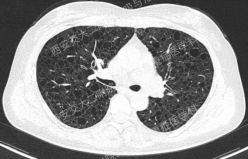

上图所示肺部囊性病变,双侧多发、大小不一,壁薄,形状不规则,呈圆形及扁平状为主,部分融合,分布多在纵隔胸膜下。入院后查血尿粪常规、肝肾功能电解质、凝血功能、血糖血脂心肌酶、BNP、肌钙蛋白正常;红细胞沉降率23mm/h,PCT、CRP正常;TB-spot阳性(阳性对照管反应水平123.49 pg/mL),TB-DNA、PPD试验、痰X-pert、痰涂片、痰培养均阴性;女性肿瘤标志物全套未见异常;结缔组织病相关指标:自身抗体ANA 1:100、CENP B阳性,CCP抗体25.1U/ml(正常参考值<17U/ml),ANCA、抗核抗体谱、体液免疫全套均阴性;血气分析大致正常,肺功能检查: FEV1占预计值78.2%,FEV1/FVC 69.55%,RV/TLC 49.62%,支气管舒张试验阴性,FeNO50 29.2ppb。